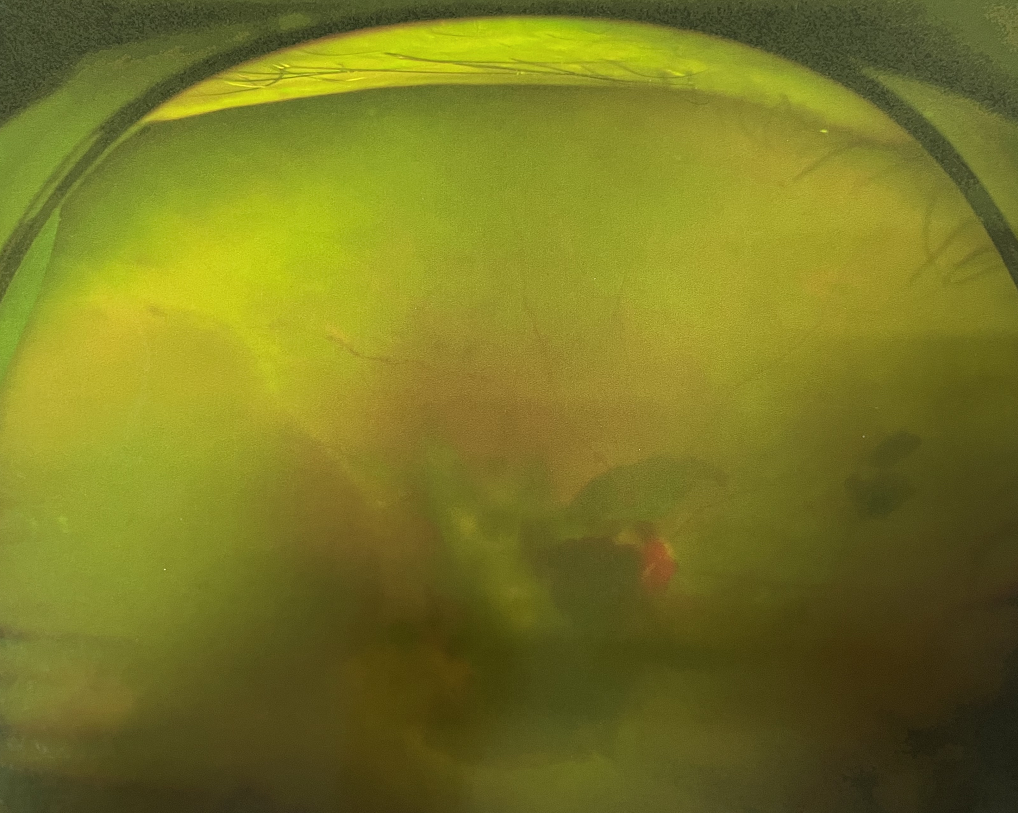

右眼術(shù)前

眼底病??茝埿』⑨t(yī)生檢查后,診斷王女士為“雙眼玻璃體積血、雙眼糖尿病視網(wǎng)膜病變V期”。(V期即5期,纖維增生期,出現(xiàn)纖維膜,可伴視網(wǎng)膜前出血或玻璃體出血。)

張小虎醫(yī)生為王女士進(jìn)行右眼玻璃體腔注藥術(shù),3天后進(jìn)行右眼23G玻璃體切割術(shù)后視力有所提升。

4個月后王女士來院取硅油,取油后視力恢復(fù)到0.6。“當(dāng)時來的時候真的只能看到模糊的影子,特別害怕覺得完了,想說眼睛估計要瞎了,沒想到手術(shù)后視力竟然提升了,現(xiàn)在也看得比較清楚了。”王女士說到。

張小虎醫(yī)生表示,糖網(wǎng)病進(jìn)展到嚴(yán)重增殖期帶來的視力損傷往往是極其嚴(yán)重的,目前王女士右眼從術(shù)前0.02恢復(fù)到術(shù)后0.6,已屬十分難得。